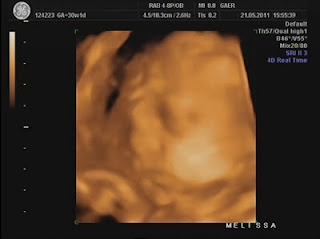

Hoje foi dia de análises e eco...

Durante a eco, percebi que a Dra ficou tempo a mais a avaliar o mesmo local e ao fim ela me explicou que viu uma lamina de água a volta do coraçãozinho da minha pricesa.

Ela me explicou que isso acontece a alguns bebés e que não devo me preocupar, que temos que fazer um exame mais detalhado para avaliar o coraçãozinho dela que será feito no Hospital São João e que hoje já trataria de marcar isso...